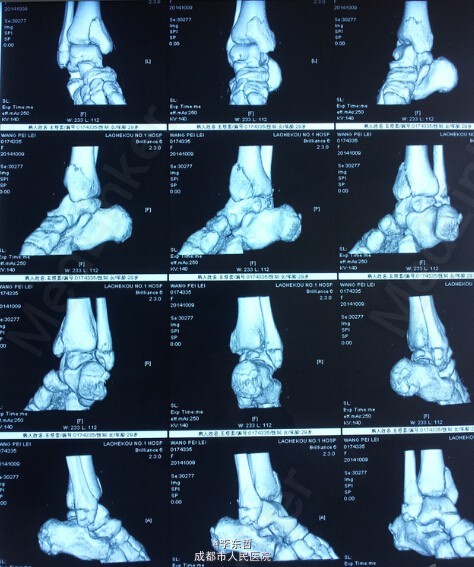

左下肢胫腓骨骨折伴右下肢内外踝骨折一例

患者,女,26岁,外伤致左下肢胫腓骨骨折、右下肢内外踝骨折,入院后右侧临时石膏固定、左侧骨骨牵引10天后,双侧同时手术,左侧胫骨采用MIPPO技术内侧钢板固定。